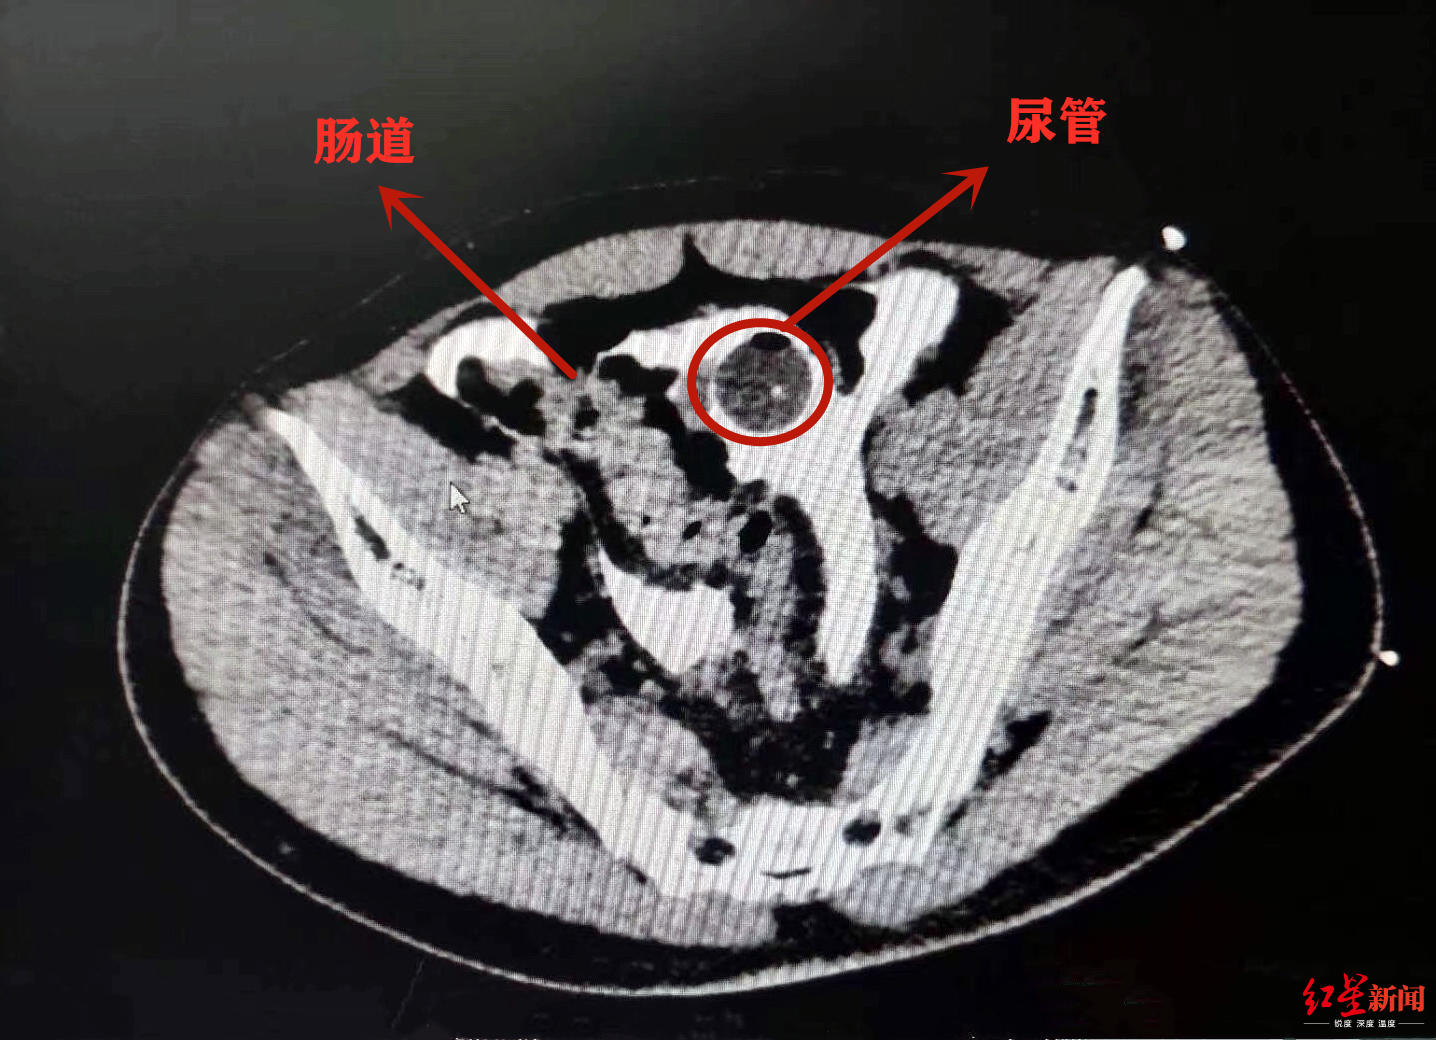

酒后憋尿摔一跤 小伙子膀胱磕破了!医生紧急修补

酒后憋尿摔一跤,成都小伙子膀胱磕破了.